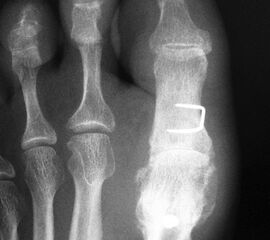

Die Röntgenaufnahmen (Abbildung 1) zeigen den Fuß einer 34 jährigen Patientin nach Exostosenabtragung. Der erhöhte intermetatarsale Winkel wurde durch eine alleinige Abtragung der Exostose nicht reduziert. Als weiterer Risikofaktor für ein Rezidiv liegt ein pathologischer Gelenkwinkel vor. Der intermetatarsale Winkel von 18 Grad kann durch eine basisnahe Osteotomie gut korrigiert werden. Da durch die gleichzeitige distale Korrektur des Gelenkflächenwinkels mithilfe einer Reverden-Green Osteotomie ein Längenverlust von ca. 2-4 mm einhergeht, bot sich als proximales Korrekturverfahren die basisnahe Open-wedge Osteotomie an, um bezüglich der Länge des Metatarsale I neutral zu bleiben (Abbildung 2). Die Kombination zweier verkürzender Verfahren (z.B. Lapidus und Reverden-Green) würden zu einem sehr kurzen ersten Strahl führen, mit dem Risiko einer Transfermetatarsalgie. Übersteigt die Verkürzung des Metatarsale I 2 mm, steigt das Risiko für die Entwicklung einer Transfermetatarsalgie deutlich an 8. Die durchgeführte Revision zeigt eine gute Stellung des 1. Strahls bei zentriert stehendem Gelenk.